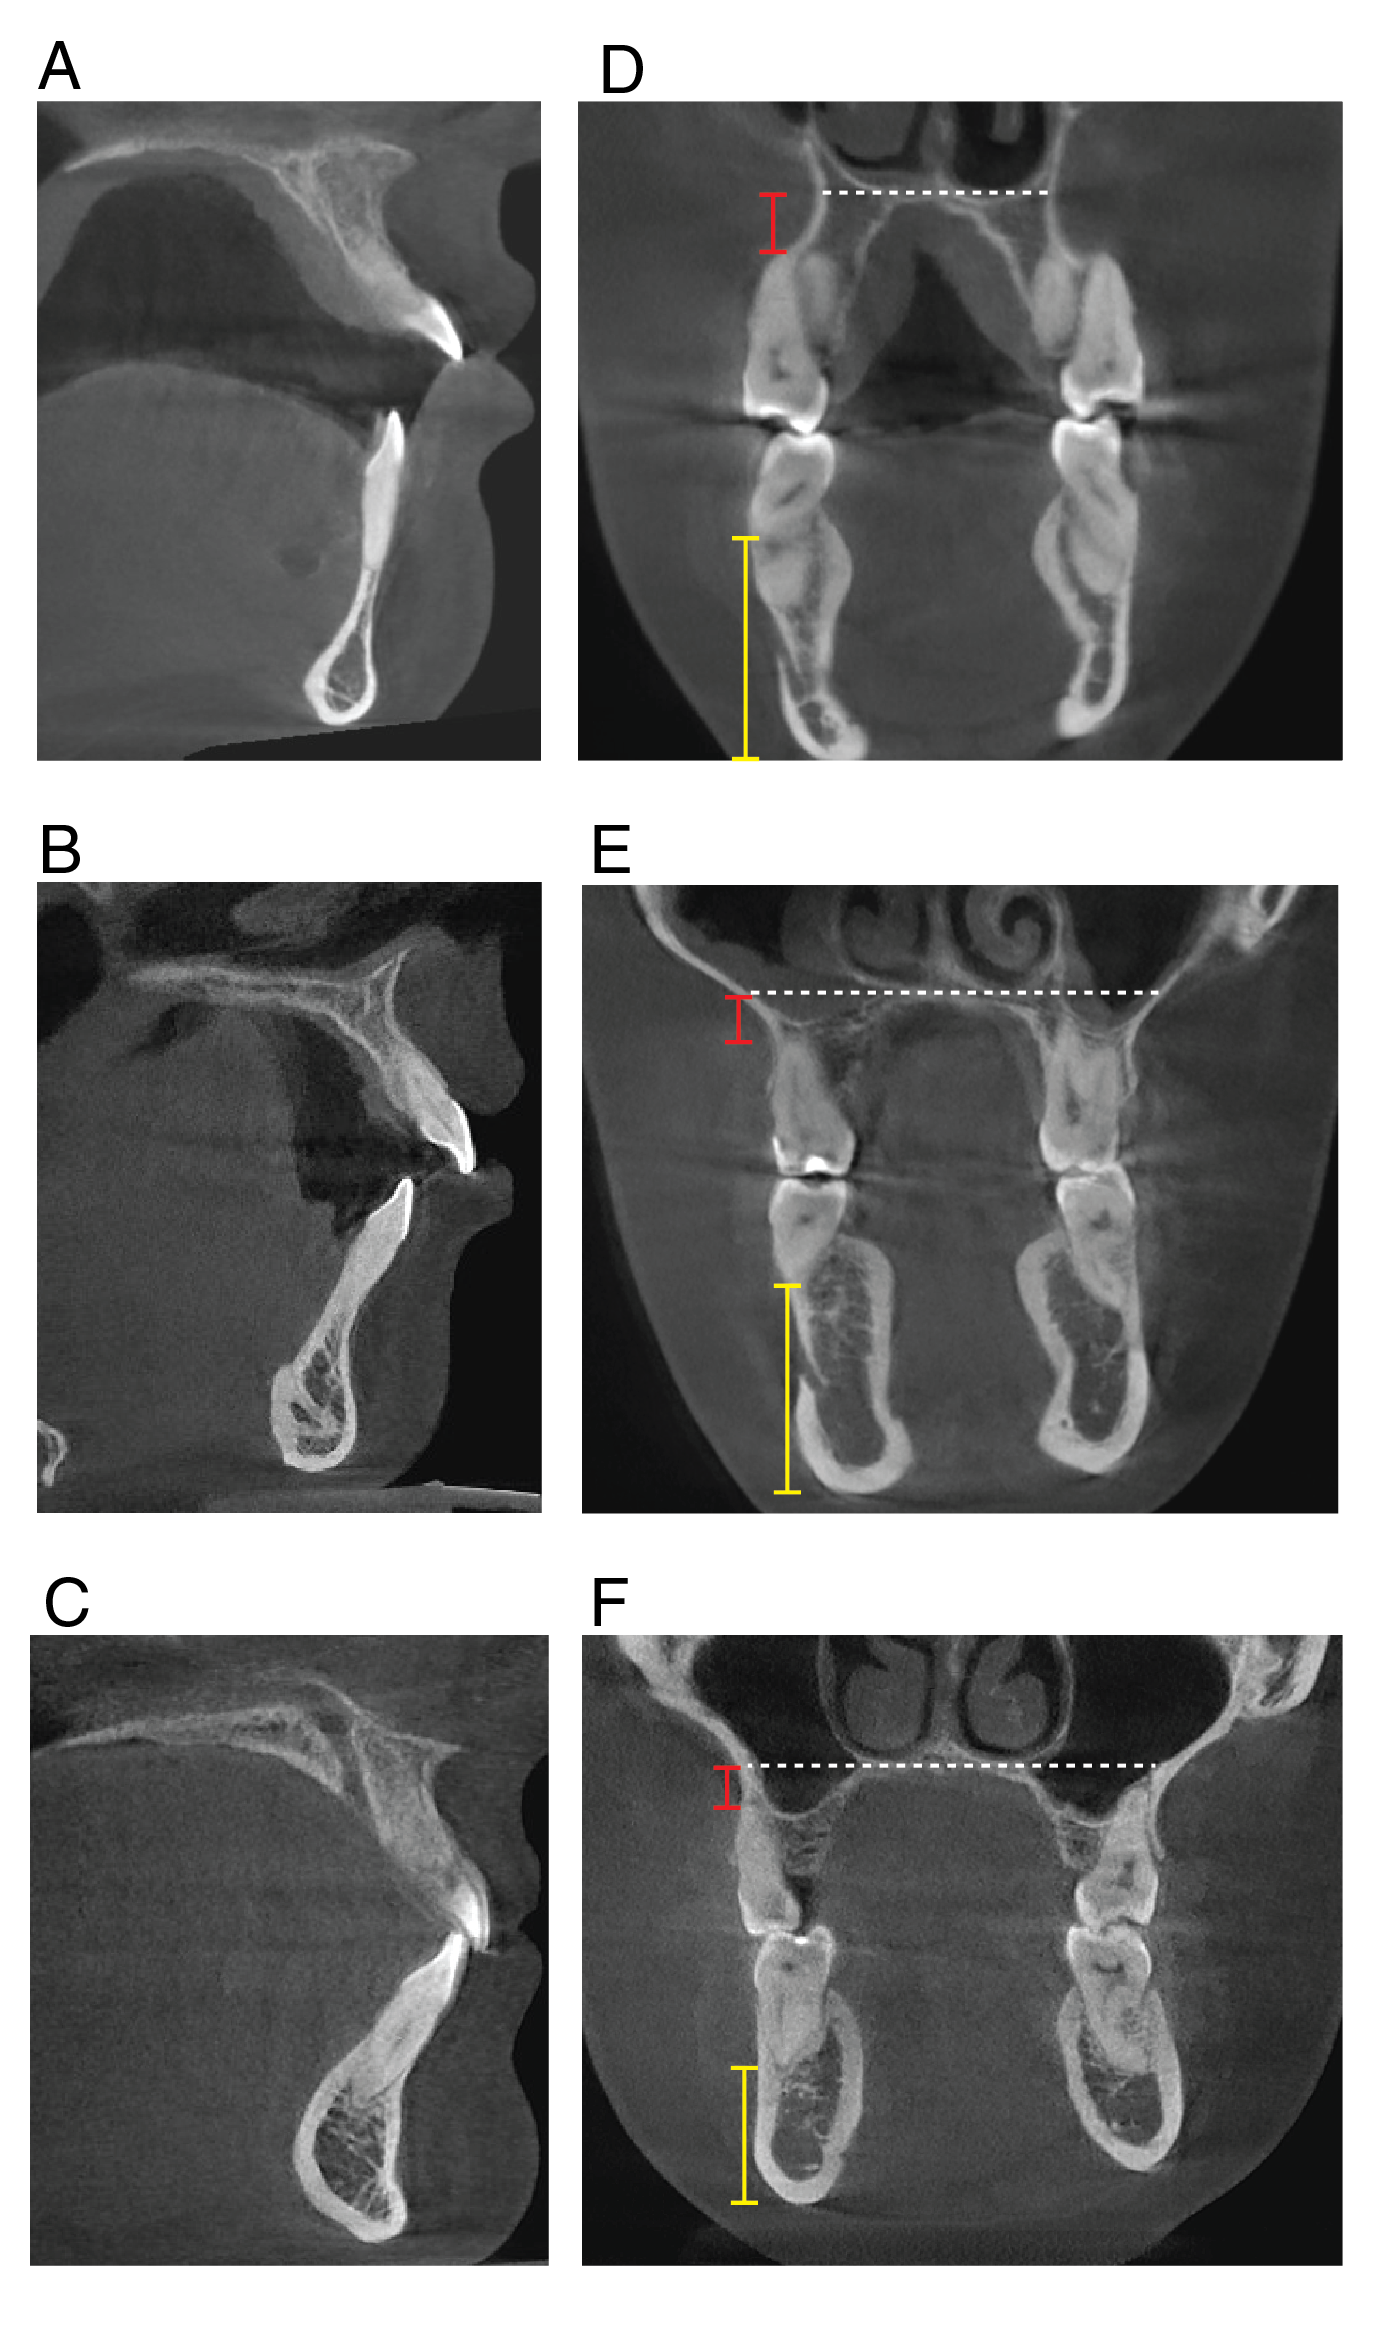

Figure 6: Condyle of a patient with Nemaline Myopathy. Radiographic images show the righ The right and left mandibular condyles of an NM patient (A), a matched open bite (B), and a matched control patient (C). The decrease in size, thinner cortical bone, less trabecular bone, and longer neck differentiate the NM patient from the matched patients.

Figure 8. Upper and lower alveolar bone, palate, and symphysis in an NM patient. Radiographic images of the NM patient (A, D), matched open bite (B, E), and matched control patients (C, F). The red bar demonstrates the distance between the palate and the apex of the first molar, while the yellow bar demonstrates the distance between the border of the mandible and the apex of the first molar.